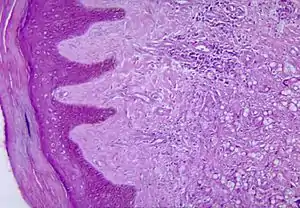

| Histopathological changes in the skin seen in lobomycosis. Source: CDC | |

Diagnosis of Lobo's disease is made by taking a sample of the infected skin (a skin biopsy) and examining it under the microscope. Lacazia loboi is characterized by long chains of spherical cells interconnected by tubules. The cells appear to be yeast-like with a diameter of 5 to 12 μm. Attempts to culture L. loboi have so far been unsuccessful.